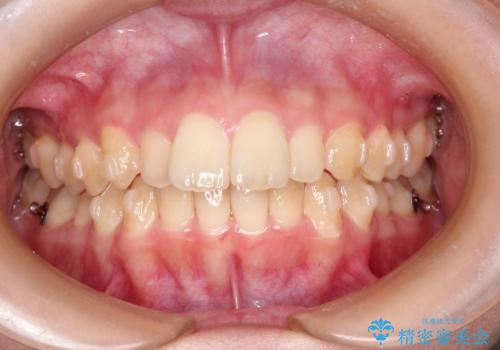

- インビザライン

- 2年

インビザラインにて上顎の歯を全体的に後方に移動させて前歯を引っ込める計画としました。

使用時間を守っていただけたので、比較的スムーズに矯正を終了することができました。